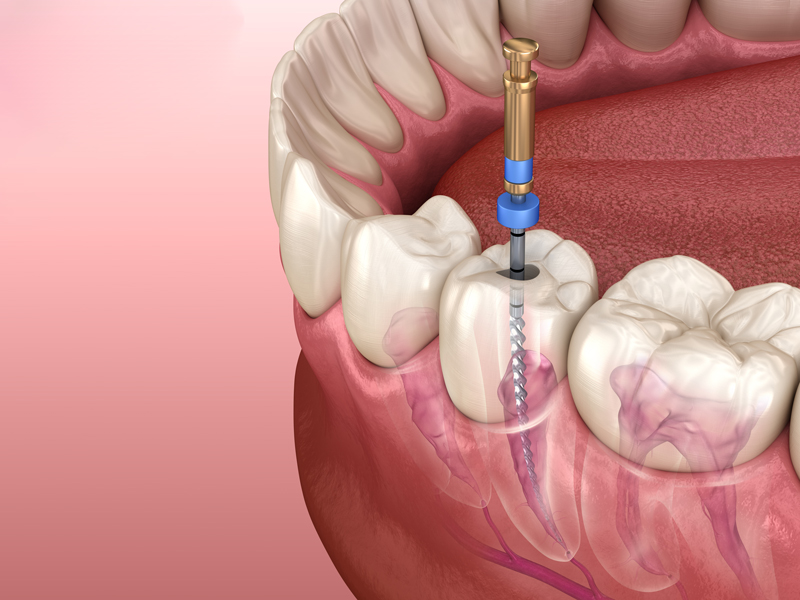

Bei der Wurzelkanalbehandlung wird das Gewebe des Zahnnervs aus dem Inneren des Zahnes entfernt und der Zahn mit einem Füllmaterial dicht verschlossen, um die Wiederbesiedlung mit Keimen zu verhindern. Der Zahnarzt legt die Wurzelkanäle frei, entfernt das Zahnnervgewebe, reinigt es und verschließt die Wurzelkanäle dann mit einem geeigneten Füllmaterial, um den darauf folgenden Verschluss durch eine Krone oder eine Füllung zu gewährleisten.

Sind in den Seitenkanälen der Wurzelspitze Bakterien oder eine Entzündung noch immer vorhanden, muss eine Wurzelspitzenresektion durchgeführt werden. Nur so kann die Infektionsquelle beseitigt und der Zahnverlust vermieden werden. Die Wurzelspitze wird dabei vom Kieferknochen aus entfernt und die Wurzelkanäle werden von unten verschlossen. Der Zahn kann im Kieferknochen erhalten bleiben.